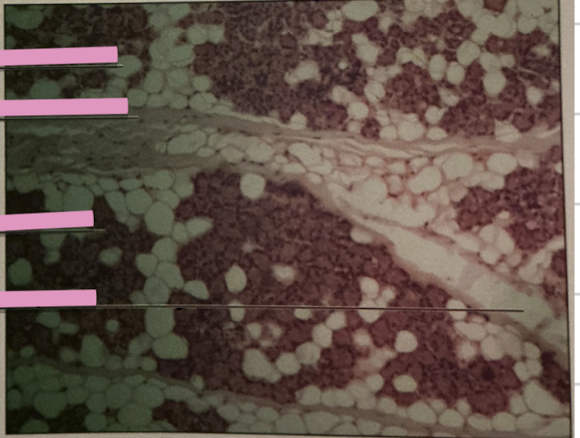

thymus

thymus

where does development of T cells occur?

Hassall’s Corpuscle

___________ sites accumulate dead T cells & involved in development of reg. T cells

spleen

spleen

macrophages. lymphocytes, entrapment/destroy old RBCs and platelets

hodgkin’s granuloma

hodgkin’s granuloma

cancer of lymph system - breakdown of red and white pulp

reed-sternberg cells

derived from B lymphocytes